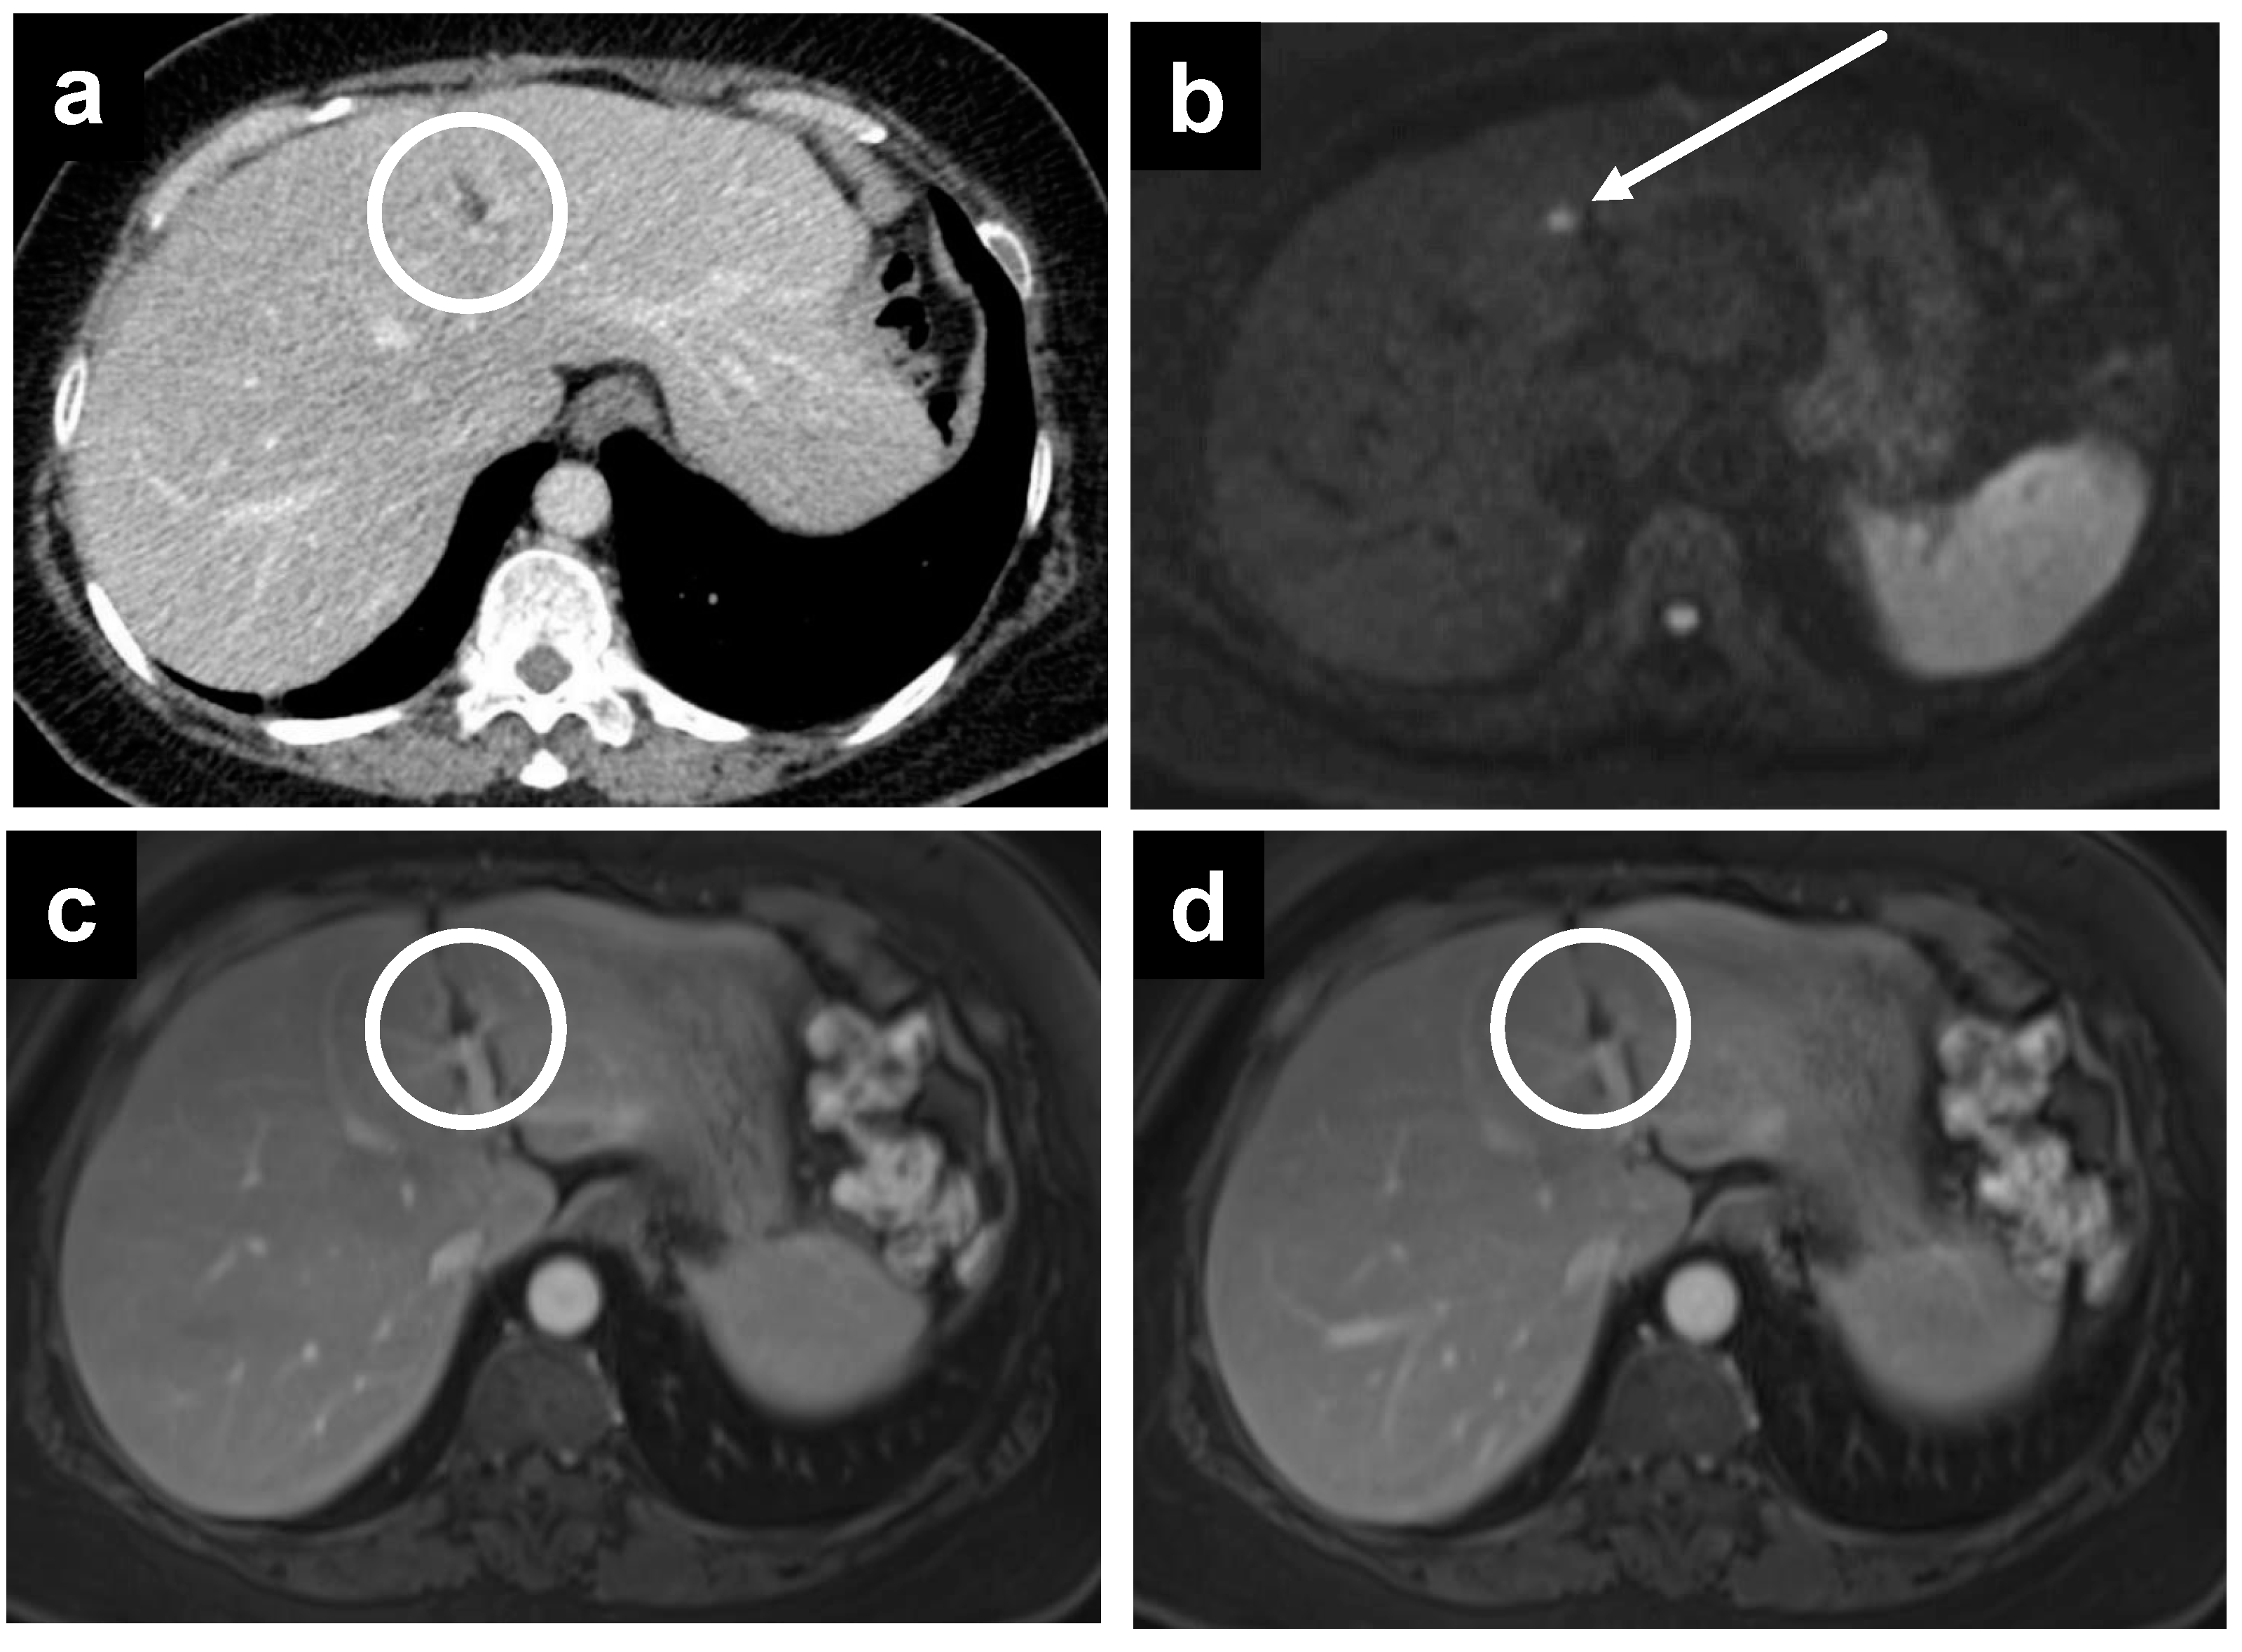

Figure 5.

A 67-year-old male with metastatic colonic adenocarcinoma and gastric serosa peritoneal deposits. The deposits are not as well seen on (a) CT, as denoted by the white circle, but are more apparent on MRI, including the (b) T2W, (c) delayed, and (d) DWI sequences secondary to the superior soft tissue contrast.